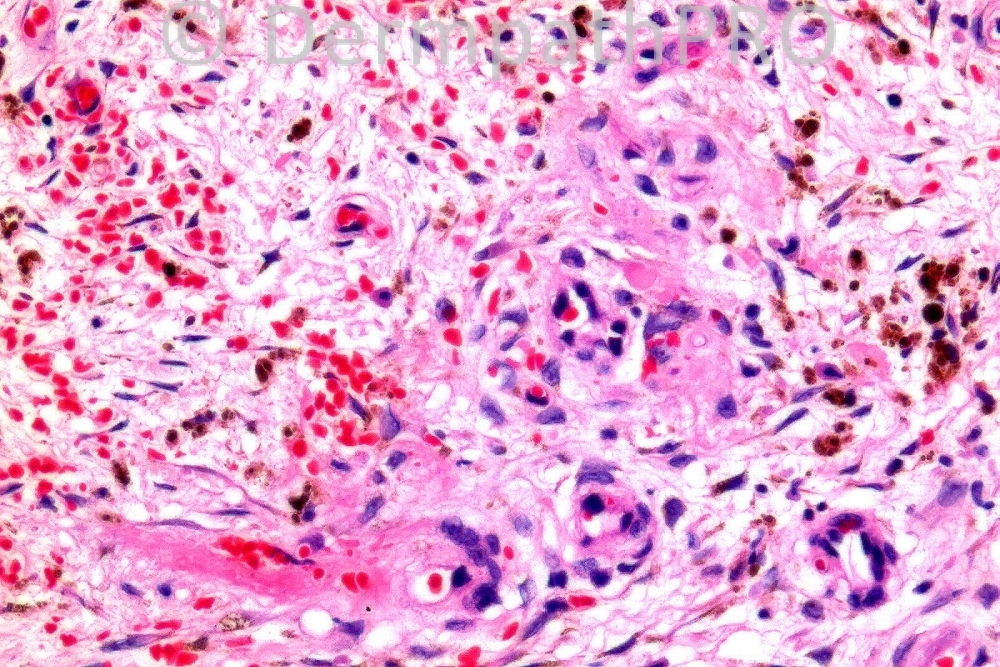

Male 85 years, lower legs, haemorrhagic keratotic lesions right lower inner leg. Chronic intermittent right ankle swelling. ?Kaposi's sarcoma.